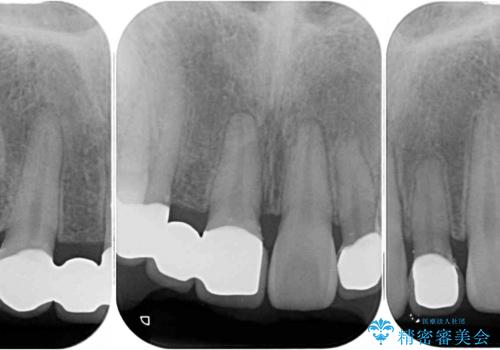

診察の結果、前歯が1本欠損しており、さらに矮小歯(通常よりも小さい歯)が1本存在していました。

欠損による前歯のスペースが大きかったため、事前にワイヤー矯正で前歯の位置を大きく動かし、その後は上下をインビザラインで整えることとしました。

矯正治療後には欠損部はオールセラミックブリッジに、矮小歯はオールセラミッククラウンにて補綴することとしました。

前歯のスペースは、堅い線維の通った歯肉があり、幅も大きかったことから、歯肉切除を行った上でワイヤー矯正により移動を行いました。また、上唇小帯も歯間部付近まで付着していたため、合わせて切除しました。

ワイヤー矯正により、インビザラインよりも早く、歯軸の向きもコントロールしながら移動させることができました。